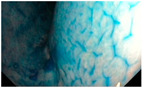

| Gastric Mucosal Pattern Category | IC-CE Example Image |

|---|---|

| Normal | ![]() |

| Suspicious | ![]() |